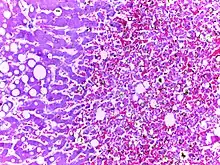

![]() | Tuberculous granuloma | Caseating granulomatous lesion with areas of amorphous granular eosinophilic necrotic debris known as caseation (on the right half) bordered by collections of epitheloid cells, Langhan giant cells and lymphocytes. | Category: Histopathology of tuberculous granuloma | Tuberculous granuloma |